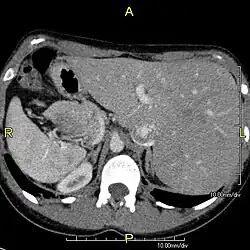

Situs inversus is found in about 0.01% of the population, or about 1 person in 10,000. In the most common situation, situs inversus totalis, it involves complete transposition (right to left reversal) of all of the viscera. The heart is not in its usual position in the left chest, but is on the right, a condition known as dextrocardia (lit. 'right-hearted'). Because the relationship between the organs is not changed, most people with situs inversus have no associated medical symptoms or complications.[1]

Effect on anatomy

The condition affects all major structures within the thorax and abdomen. Generally, the organs are simply transposed through the sagittal plane. The heart is located on the right side of the thorax, the stomach and spleen on the right side of the abdomen and the liver and gall bladder on the left side. The heart's normal right atrium occurs on the left, and the left atrium is on the right. The lung anatomy is reversed and the left lung has three lobes while the right lung has two lobes. The intestines and other internal structures are also reversed from the normal, and the blood vessels, nerves, and lymphatics are also transposed.

If the heart is swapped to the right side of the thorax, it is known as "situs inversus with dextrocardia" or "situs inversus totalis". If the heart remains on the normal left side of the thorax, a much rarer condition (1 in 2,000,000 of the general population), it is known as "situs inversus with levocardia" or "situs inversus incompletus".

Diagnosis of situs inversus can be made using imaging techniques such as x-ray, ultrasound, CT scan, and magnetic resonance imaging (MRI).[9]